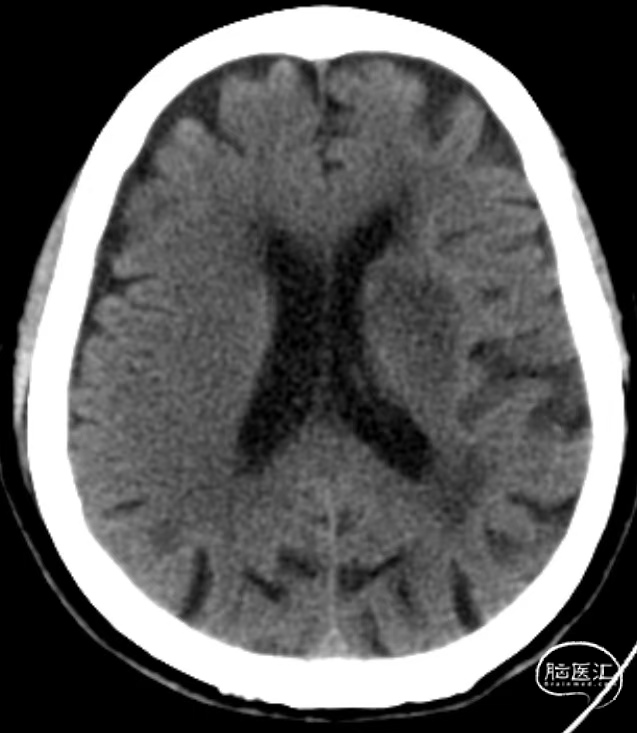

入院时CT:ASPECTS 10分。

术前MRI

术前MRA:左侧大脑中动脉闭塞。